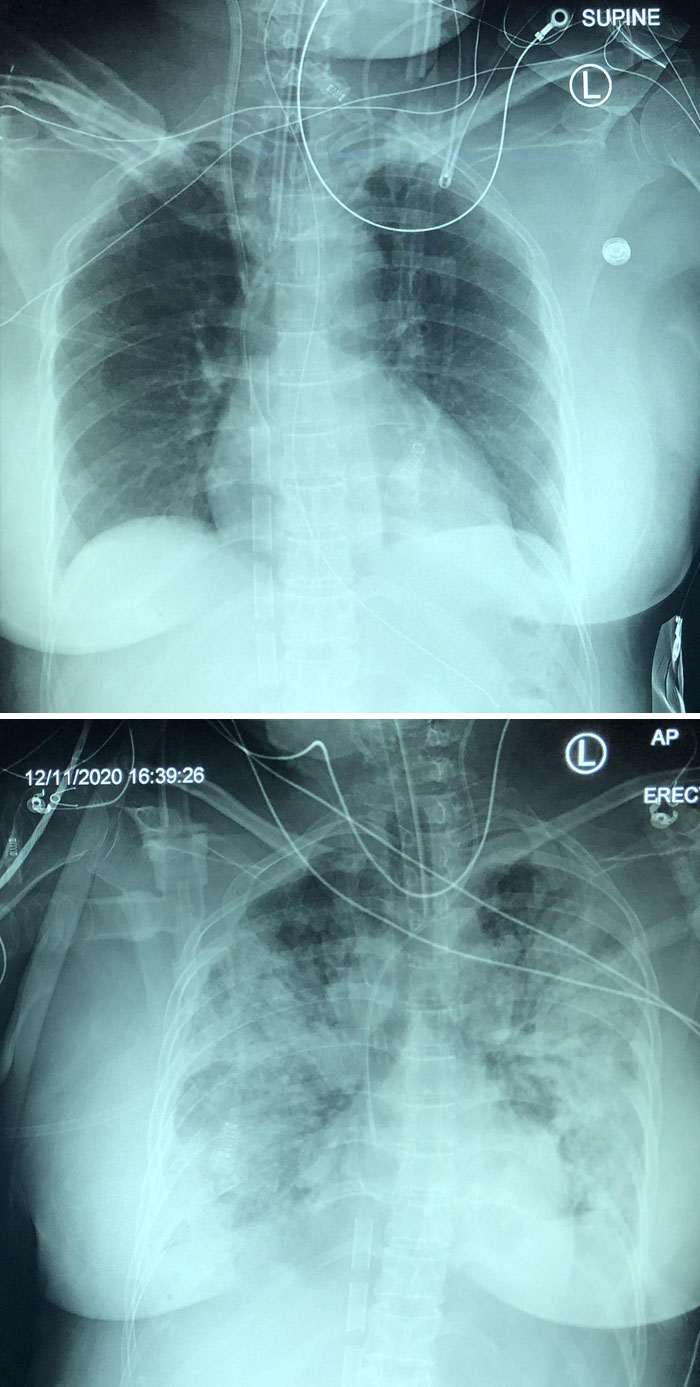

Урон легким от коронавируса Covid-19 за пять дней